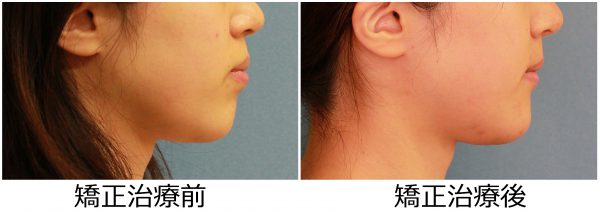

27歳 女性 「 ねじれ歯、出っ歯を治したい 」 ( 翼状捻転 )

27歳の 女性です

「 ねじれ歯 と ”出っ歯” を治したい 」との事で来院されました。

上の前歯が ねじれて 傾斜しているため

前歯だけが 目立ってしまいます。

前歯のねじれを鳥の翼に例えて、翼状捻転と呼ばれる状態です

前歯も傾斜しているため ”出っ歯” 感も強いです。

とにかく「ねじれて ”出っ歯”な 前歯が目立つのが嫌だ」との事でした。

捻じれと 出っ歯を治したいとの事で矯正治療を開始しました。

翼状捻転を伴う 上顎前突症 です。

ねじれと ”出っ歯”を治したいとの事で

上下左右の 抜歯を行い 前歯を後方に移動させました。

2018年の7月4日にスタートして 2019年の10月16日に 終 了しました。

治療期間は 15か月でした。

抜歯により、前歯の捻じれと 出っ歯感が解消しました。

前歯は大きく下がりました。

前歯のねじれは改善し、大きく下がりました

前歯が大きく下がったことで、口もとの 印象が 大きく変わり

口もともスッキリと変化しました。

素敵な笑顔になりました! (#^.^#)

27歳 女性 叢生を伴う 上顎前突症 治療期間15か月 唇側矯正装置(ホワイトワイヤー)を使用した上下顎第一小臼歯抜歯治療 参考治療費 約65万円 (精密検査から終了まで) 矯正治療に伴う副作用の歯肉退縮、知覚過敏、失活、歯根吸収などは認められませんでした。